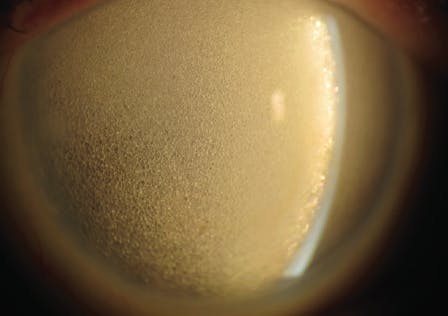

Another type of particulate glaucoma, perfluorocarbon liquid (PFCL) droplet–related glaucoma, occurs if medium-term removal of perfluoro-n-octane is inadequate after its use for inferior retinal detachment or nasal, temporal, and inferior giant retinal breaks.7,8 PFCL often becomes trapped in the zonules, residual peripheral vitreous, epiretinal membranes, and capsular bag (Figure 2).

Figure 2. PFCL droplets in the inferior anterior chamber and posterior to the lens before intraoperative removal of medium-term perfluoro-n-octane.